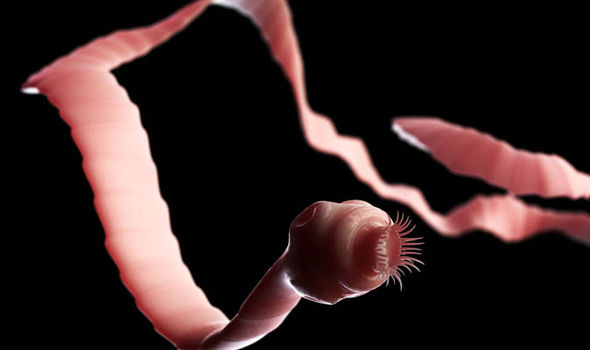

Бычий цепень

Еще один самый длинный глист в человеке — бычий цепень, относящийся также к ленточным червям. Еще одно распространенное название данного гельминта — солитер. Длина одной особи этого червя может достигать до 12 метров, а складывается она из размеров члеников, которых в одной особи насчитывается до 5 000! На сколексе (головке) бычьего цепня присутствуют 4 присоски, не имеющие крючьев. При их помощи гельминт присасывается к стенкам тонкого кишечника, где может прожить до 20 лет, выделяя во внешнюю среду вместе с калом яйца. Жизненный цикл этого длинного глиста состоит из двух фаз: в виде яйца и личинки он обитает в организме крупного рогатого скота, а затем через зараженное мясо, не подвергшееся необходимой кулинарной обработке, попадает в кишечник человека. Гельминтоз, который вызывает бычий цепень, называется тениаринхоз. Он выражается в механическом повреждении стенок тонкого кишечника, отрицательно влияет на моторную и секреторную функции кишечника. Болевые ощущения возникают при прохождении члеников паразита через баугиниеву заслонку и напоминают приступы аппендицита. Больной испытывает постоянное чувство голода, у него развивается булимия. Чаще всего проблема гельминтоза обнаруживается при анализе кала, где присутствуют членики бычьего цепня.

Паразит – бычий цепень

1. Форма. В среднем длина солитера составляет 7-15 метров, а ширина 5 сантиметров.

2. Части паразитирующего организма. Строение солитера довольно простое – головка с присосками, шея и созревшие сегменты.

3. Длительность жизни. Находясь в благоприятных условиях внутри организма, срок жизни глиста составляет до 15 лет.

Бычий цепень – белый ленточный глист. И это не какая-то мизерная острица , его средняя величина колеблется в пределах от 4 до 10 метров. Были зафиксированы случаи, когда особо прожорливые паразиты достигали 22 метров. Ширина бычьего цепня – 5-7 миллиметров.